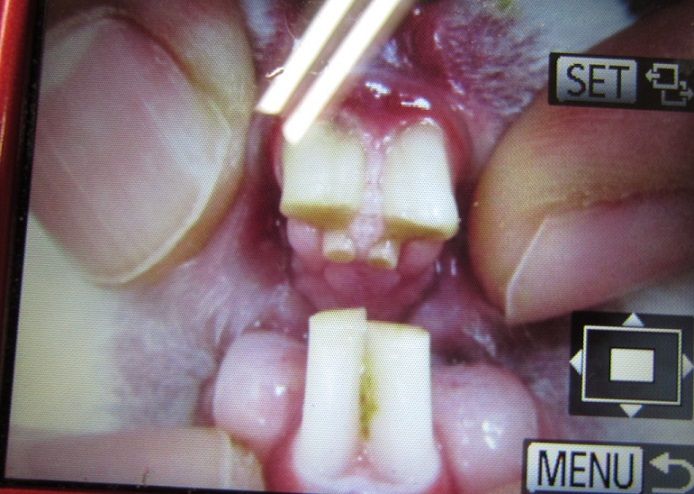

忘れないためにカルテに貼ってあったの撮らせてもらいました(。--)ノ